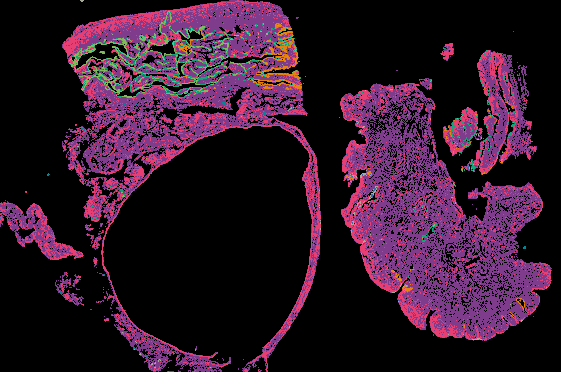

Ovarian Cancer with Annotation - LSP15327